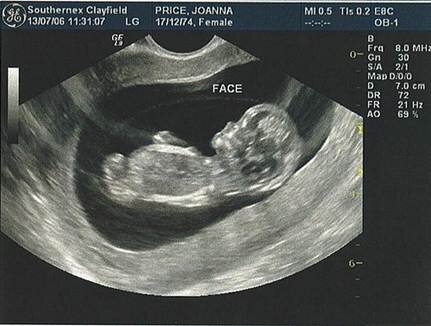

Вредно ли УЗИ для плода ?

Это звук настолько высокий, что он находится за пределами человеческого восприятия. Это обычные звуковые волны, как разговор или музыка, например, но частота колебаний этих волн выше, чем может услышать ухо человека. Как любой звук, он проникает сквозь препятствия, отчасти от них отражаясь (крикните в горах, они вернут вам эхо, с ультразвуком происходит то же самое). Ультразвуковой аппарат испускает сигнал, и он отражается (дает эхо) от разных тканей с разной силой, именно это эхо и регистрируется, превращаясь в картинку. Воздействие на плод обусловлено этими звуковыми волнами. Маловероятно, что эмбрион может их слышать, он же будущий человек, и слух у него будет человеческий, не способный слышать столь высокие звуки. Надо сказать, что до 16-17 недель орган слуха вовсе недостаточно развит, для того чтобы слышать хоть какие-то звуки. Часто во время проведения обследования можно увидеть, как малыш отворачивается от датчика, но это скорее связано с его давлением на переднюю брюшную стенку, чем влиянием самого ультразвука на плод.

Стоит помнить, что это довольно молодой метод исследования, и мы не знаем отдаленных последствий, как именно может отразиться УЗИ на беременных женщинах и на будущих поколениях. Возможно, эти опасения и беспочвенны, но не стоит настаивать на проведении 3D и 4D УЗИ, при которых сила ультразвука больше, только для того, чтобы увидеть своего малыша - достаточно обычного обследования. С другой стороны именно ультразвук стал тем методом исследования, который приоткрыл постороннему взгляду нерожденного ребенка, и дал возможность вовремя заметить серьёзные отклонения в развитии плода и принять меры, предотвращая осложнения как самой беременности, так и родов. Отказаться от УЗИ при беременности можно, нет такого закона, который заставил бы человека делать то или иное обследование. Но с другой стороны, возможно, именно эта способность может спасти вас и вашего ребенка от серьёзных осложнений, ибо как иначе заподозрить, например, неправильные положения плода, врожденные пороки развития у плода, предлежание плаценты и другие проблемы, которые могут привести в родах к настоящим катастрофам…?